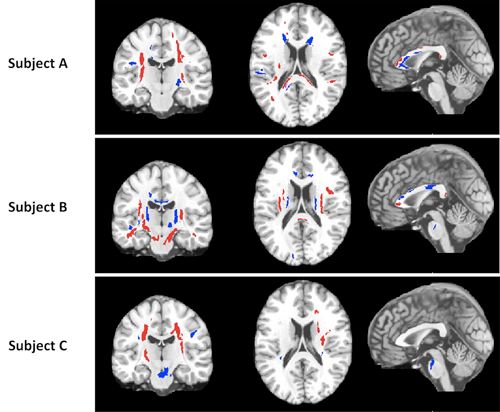

Diffusion tensor imaging detected abnormalities in the brain among subjects with mild traumatic brain injury.